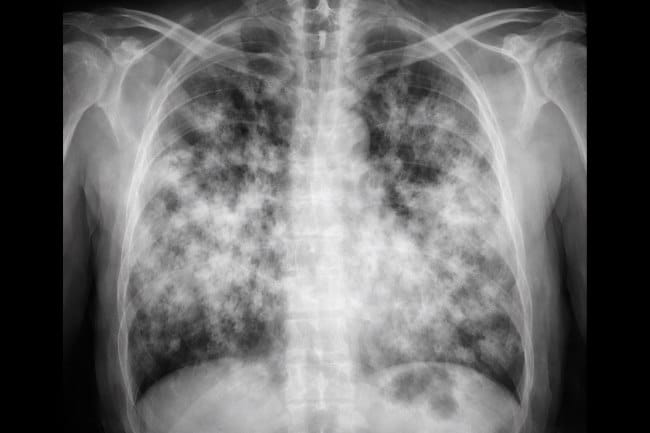

Paru-paru basah atau pneumonia adalah kondisi peradangan pada jaringan paru akibat infeksi. Kondisi ini bisa dialami siapa saja, terutama bila daya tahan tubuh sedang menurun. Karena itu, mengenali kebiasaan yang menyebabkan paru-paru basah menjadi langkah penting untuk menjaga kesehatan Anda dan keluarga.

Paru-paru basah terjadi saat bakteri, virus, atau jamur, masuk melalui saluran napas lalu berkembang di jaringan paru. Proses ini bisa dipicu oleh berbagai faktor, salah satunya kebiasaan sehari-hari yang tanpa disadari melemahkan pertahanan tubuh.